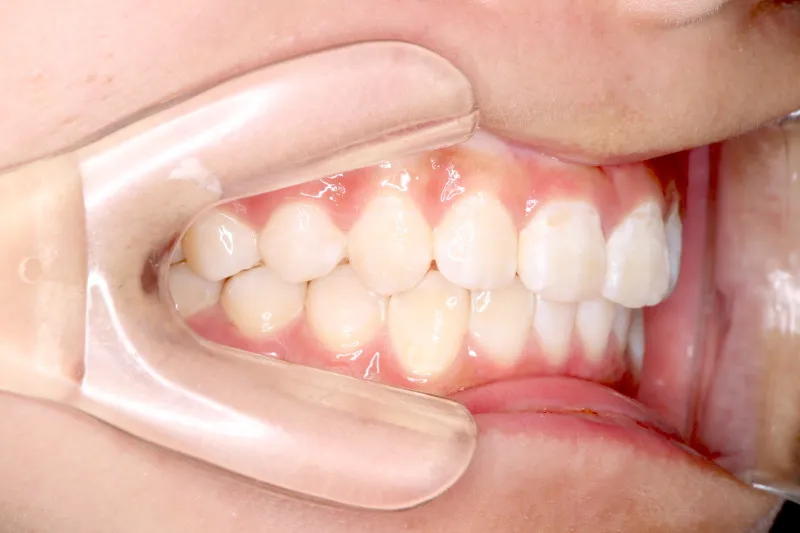

治療終了後